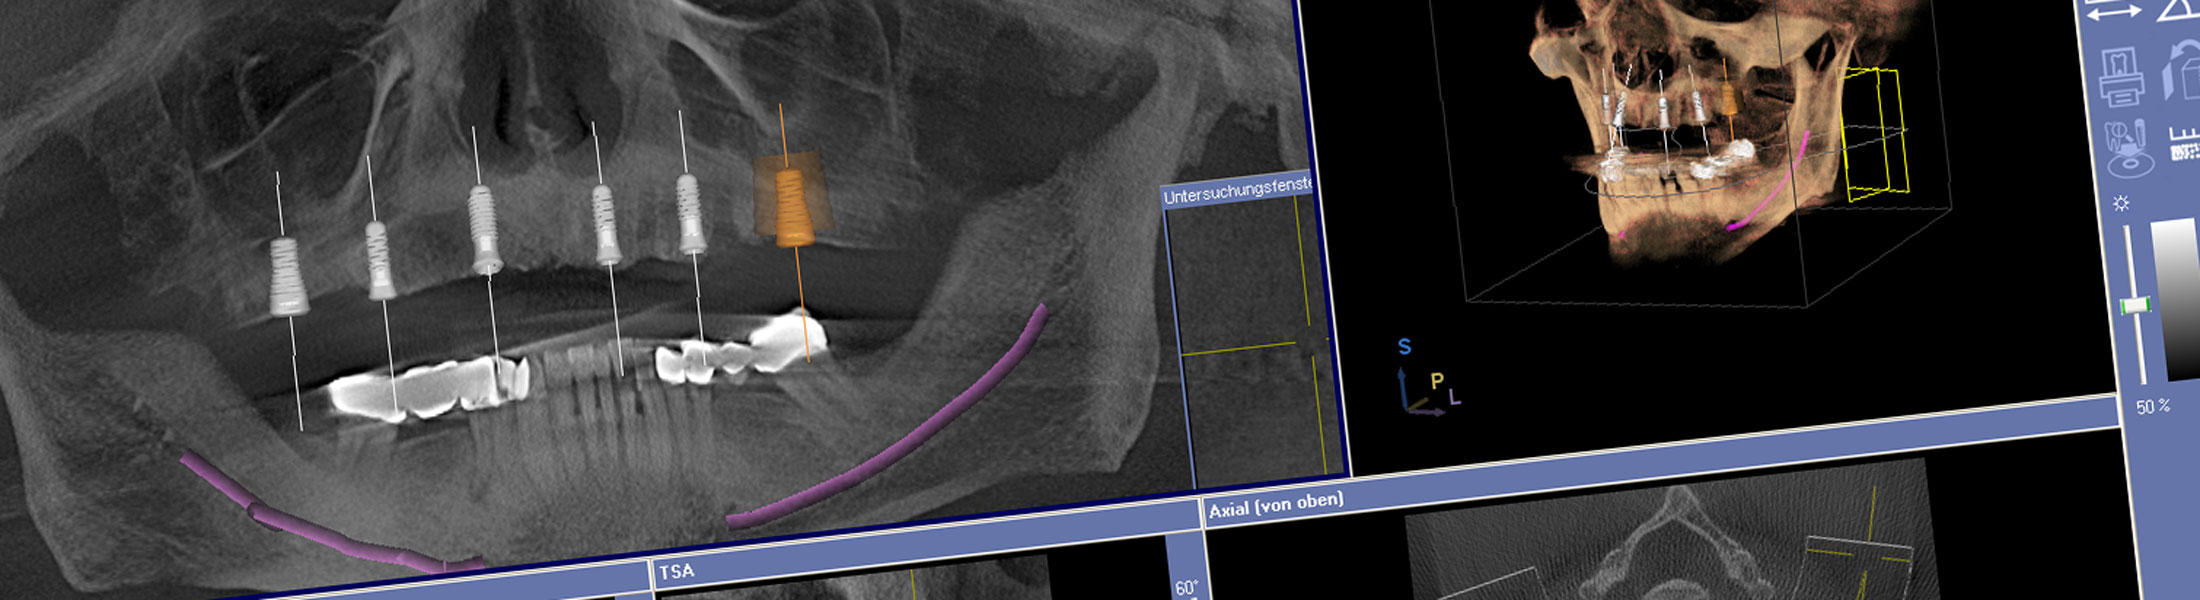

In besonderen Fällen nutzen wir die digitale Volumentomographie (DVT) bzw. die Computertomographie (CT), um mit dreidimensionalen Aufnahmen des knöchernen Gesichtsschädels schon vor einem Eingriff das Knochenangebot, die Knochenqualität und individuelle Besonderheiten zu erkennen. Mit den gestochen scharfen 3-D-Ansichten können wir die knöchernen Strukturen des Oberkiefers und des Unterkiefers, ausgesuchte, einzelne Segmente oder komplexe Zusammenhänge detailliert darstellen. Diese neue Technik eröffnet uns zuverlässige diagnostische und therapeutische Möglichkeiten in der Implantologie, Prothetik, Kieferorthopädie und Zahnerhaltung.